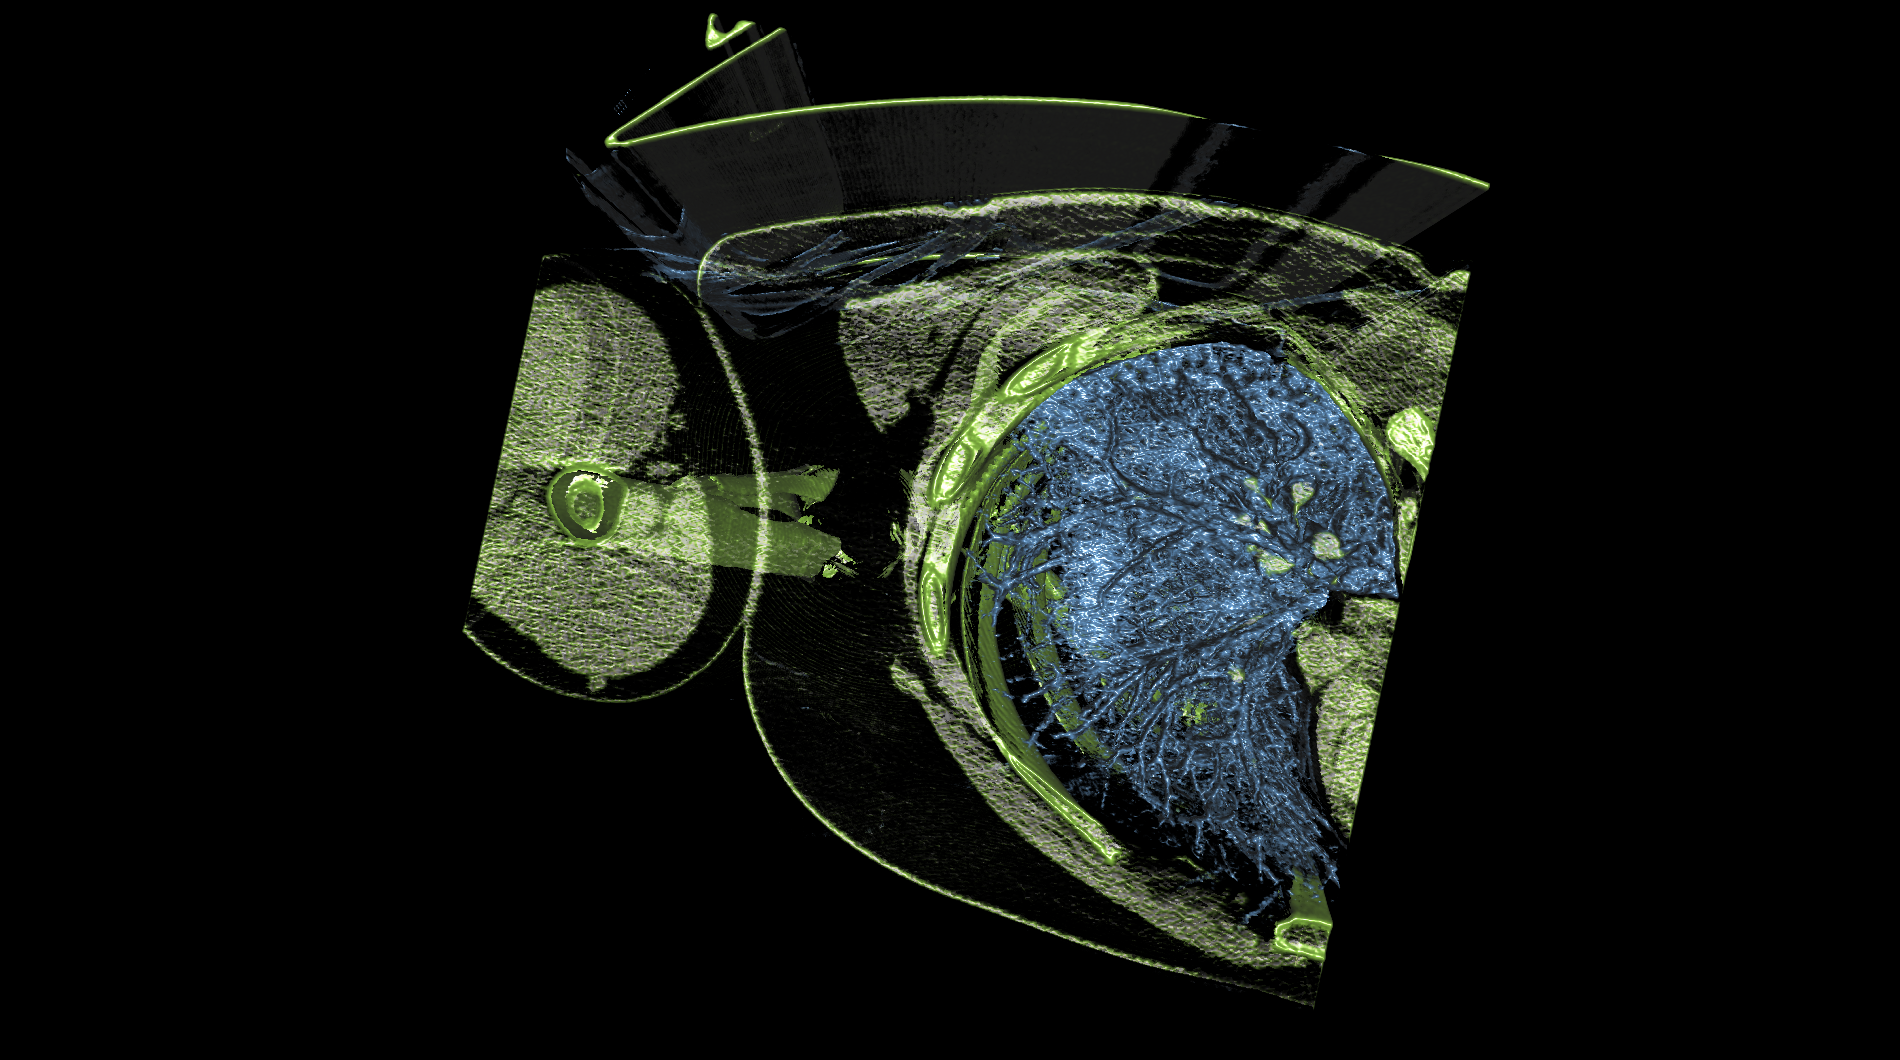

medical-03

The medical-03 viewset demonstrates the performance of several medical visualization volume rendering techniques. The first is "slice rendering", where many 2D slices are projected through the volume and composited on the screen. The second is "raycasting" where rays are projected through the volume accumulating the final pixel color. Two different transfer functions are used: 1D, where the density is used to look up each voxel color, and 2D, where density and gradient magnitude are used to look up each voxel color. A clipping plane is used in several tests. The Tuvok visualization library is used for rendering.

medical-03 composite score: 25.67

The composite score is a weighted geometric mean of the subtest scores. See the table below for subtest weights and FPS scores for this run.

Subtest results

Click on each thumbnail image below to display the subtest's screen grab.

The results table above includes the details about each test within a viewset. Viewsets are often comprised of many tests which produce a frame rate. Frame rate is computed as the average Frames Per Second (FPS), or the total number of frames rendered divided by the time in seconds to render those frames. These FPS values are then used to compute the composite score using the weights for each test.